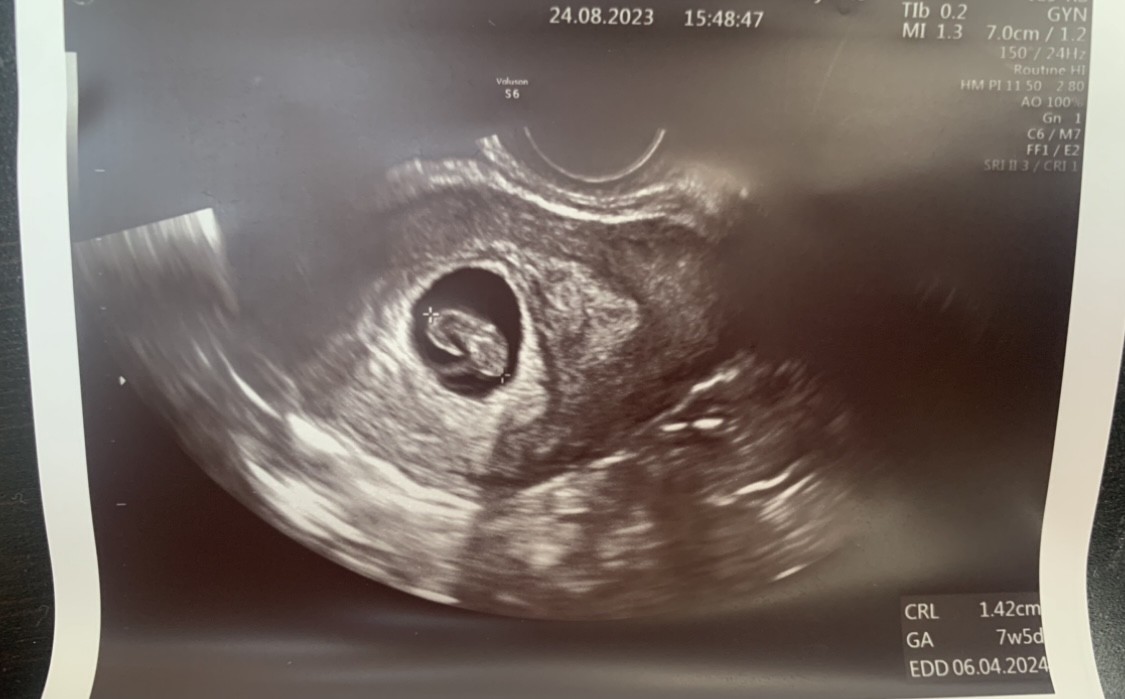

Słuchajcie beta HCG 6w+1d 78,5tysiąca przy czym zakres jest do chyba 33 tysięcy.To się nie dziwię dlaczego się tak beznadziejnie czuje i wymiotuję.Jak to jest u Was z betą?? Ja żałuję,że z synem nie zrobiłam to miałabym porównanie